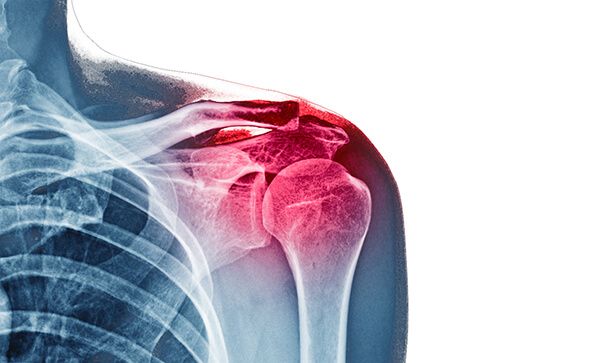

3. Advanced Imaging Techniques (If Needed)

- X-rays to examine bone structure and joint alignment

- MRI scans to detect tendon, muscle, or ligament injuries

- Ultrasound for real-time visualization of soft tissue problems